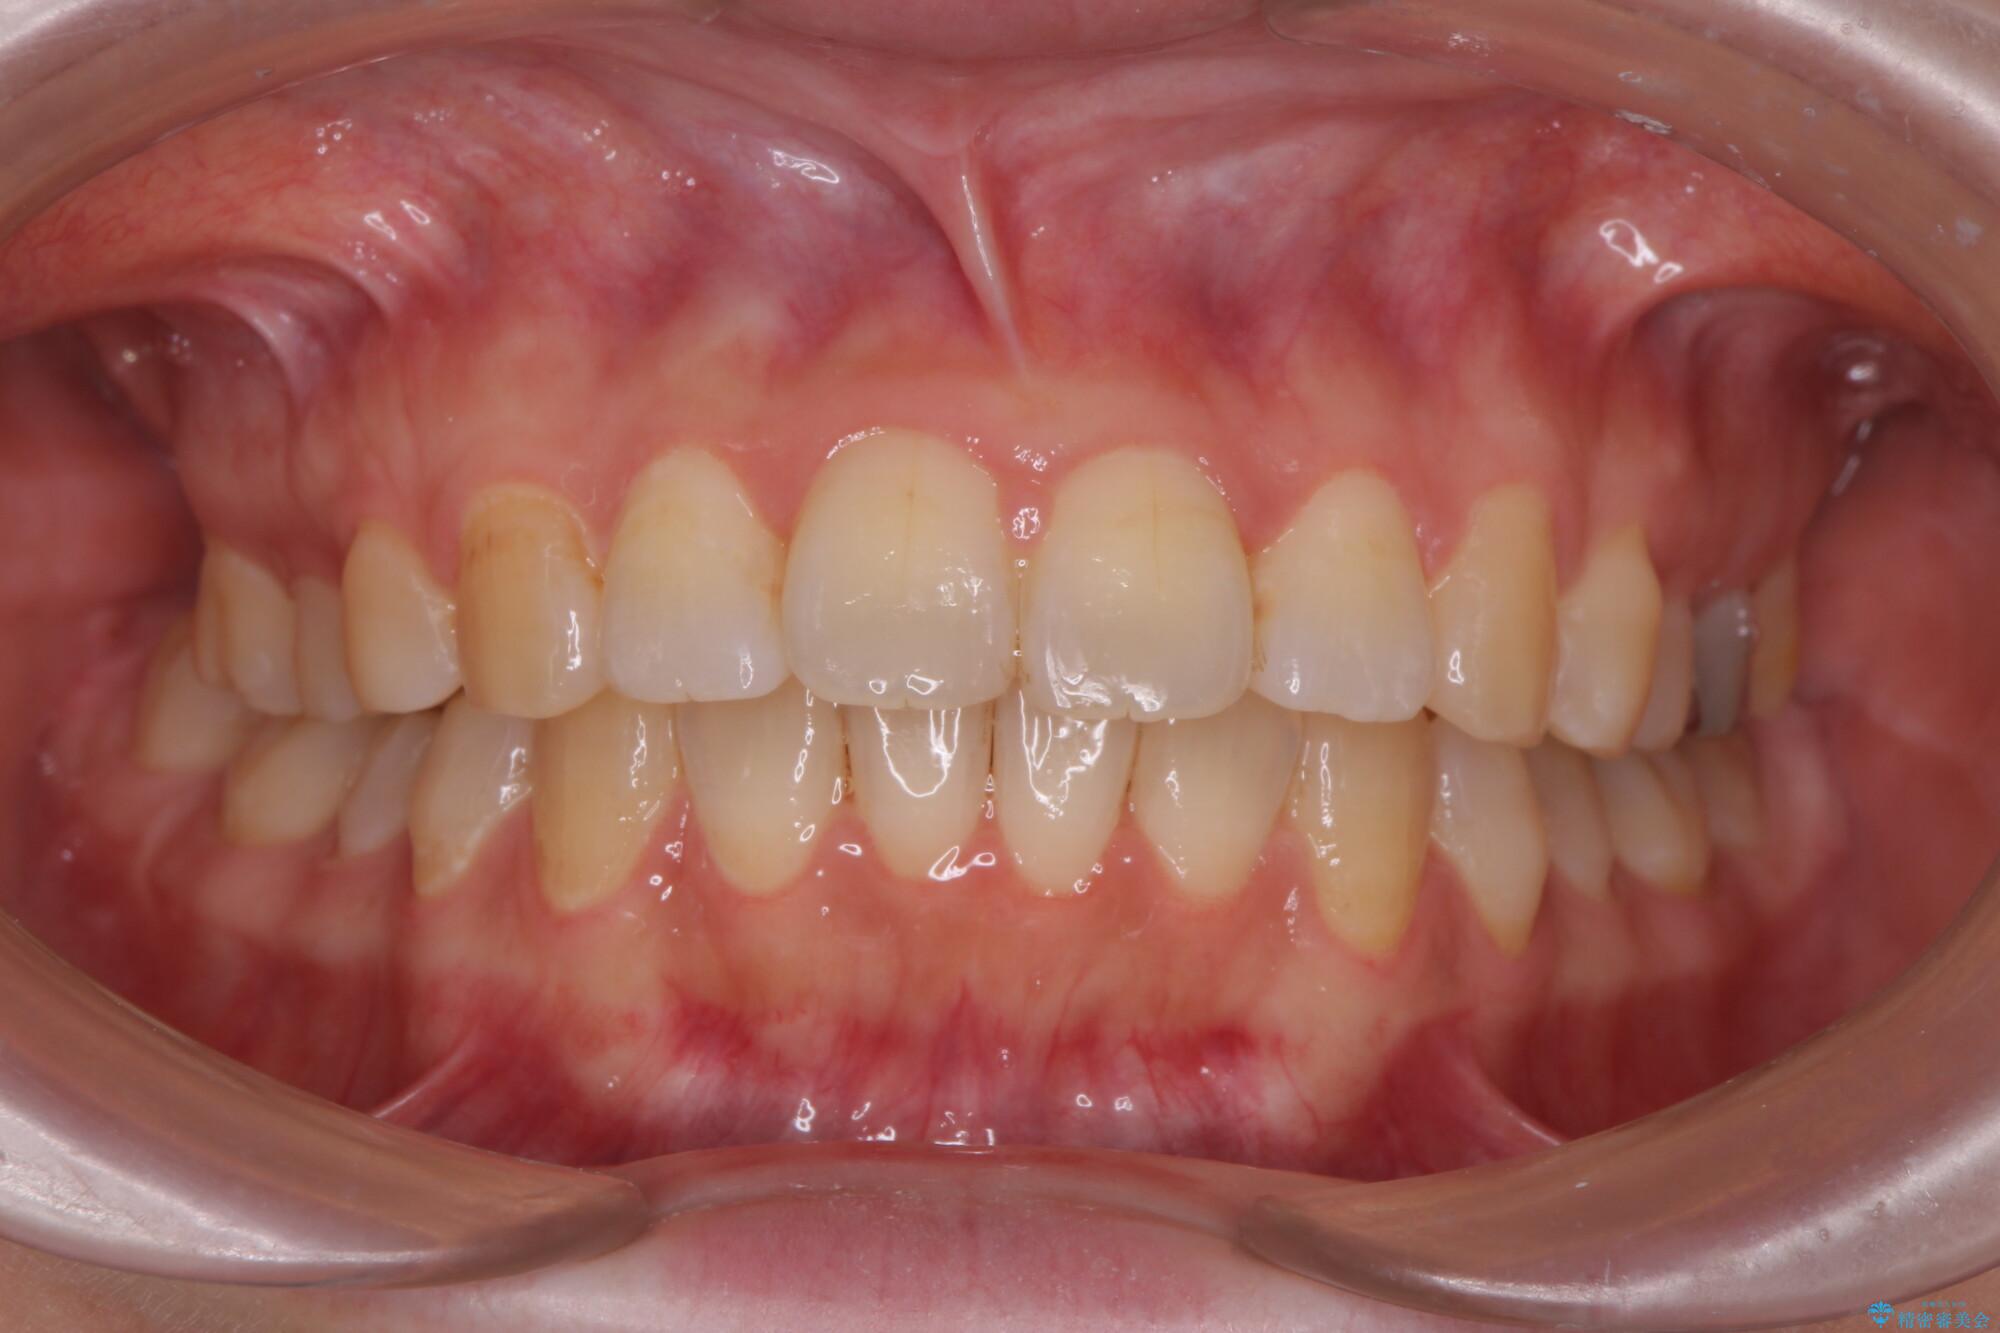

治療後

傾いた前歯、インビザラインで改善 治療後画像 傾いた前歯、インビザラインで改善 治療後画像 傾いた前歯、インビザラインで改善 治療後画像 傾いた前歯、インビザラインで改善 治療後画像

治療を終えて

非抜歯のため、歯と歯の間を少し削ることでスペースを確保し、がたつきを改善しました。

見た目の印象も変化し、大変ご満足いただけました。